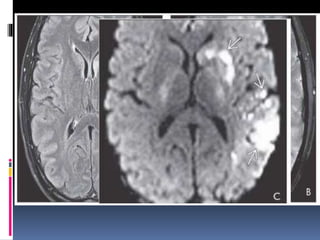

MRI

Expedited protocol with only FLAIR,T2*,DWI

 DWI- Positive in > 95% cases within minutes

Hyperintense on DWI

Hypointense on ADC mapping

Mismatch between FLAIR & DWI – PENUMBRA